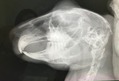

術前検査のレントゲン

特に問題ありません。

※クリックで拡大見れます。